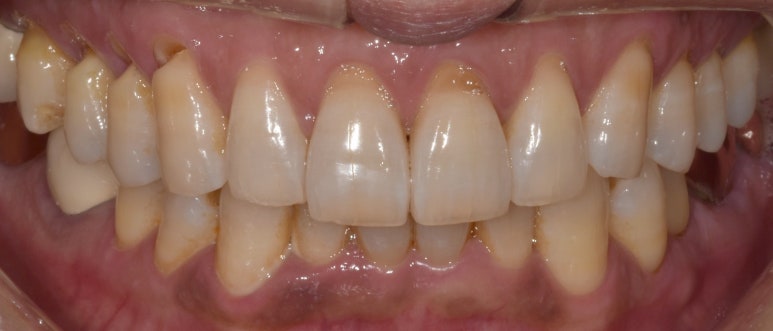

치경부마모증 실제 사례

53세 남성

촬영일자: 2022-09-30

위 사진은 치경부마모증이 심해진 환자분의 실제 사진인데요.

사진상으로 왼쪽 위 치아쪽(실제로는 오른쪽 위) 치경부 부분이 노출되고 패인 모습이 보이시죠?

아마 사진의 환자분께선 시린 증상을 많이 느끼셨을거예요.